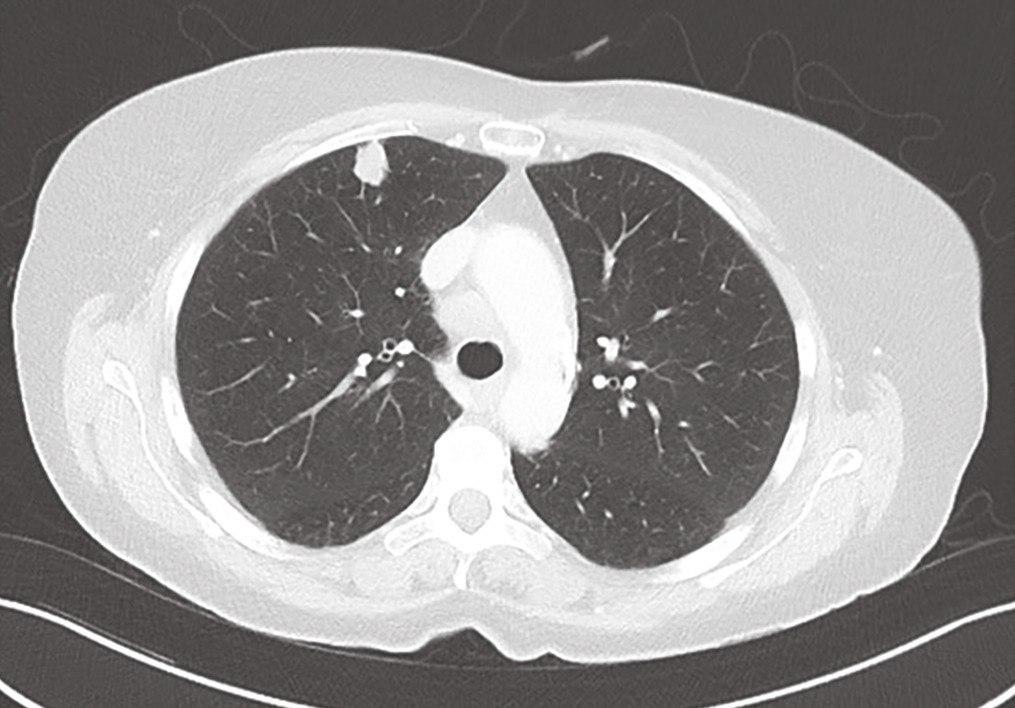

Une femme de 70 ans, tabagique sevrée à 45 paquets-années, présente un syndrome médullaire d’évolution rapide (3 semaines). L’imagerie par résonance magnétique montre une masse fusiforme intramédullaire au niveau de C7 (fig. 1 ). Le bilan lésionnel met en évidence un nodule pulmonaire évocateur de lésion néoplasique primitive (fig. 2 ), et plusieurs autres lésions secondaires : cérébrale, ganglionnaires et hépatiques. La biopsie hépatique confirme le diagnostic de carcinome pulmonaire (marqueur TTF-1 positif) métastatique peu différencié. L’évolution rapidement progressive a conduit à la mise en place de soins palliatifs exclusifs.